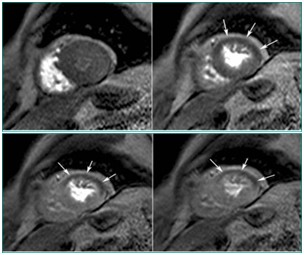

心肌灌注(病例-心肌梗死)